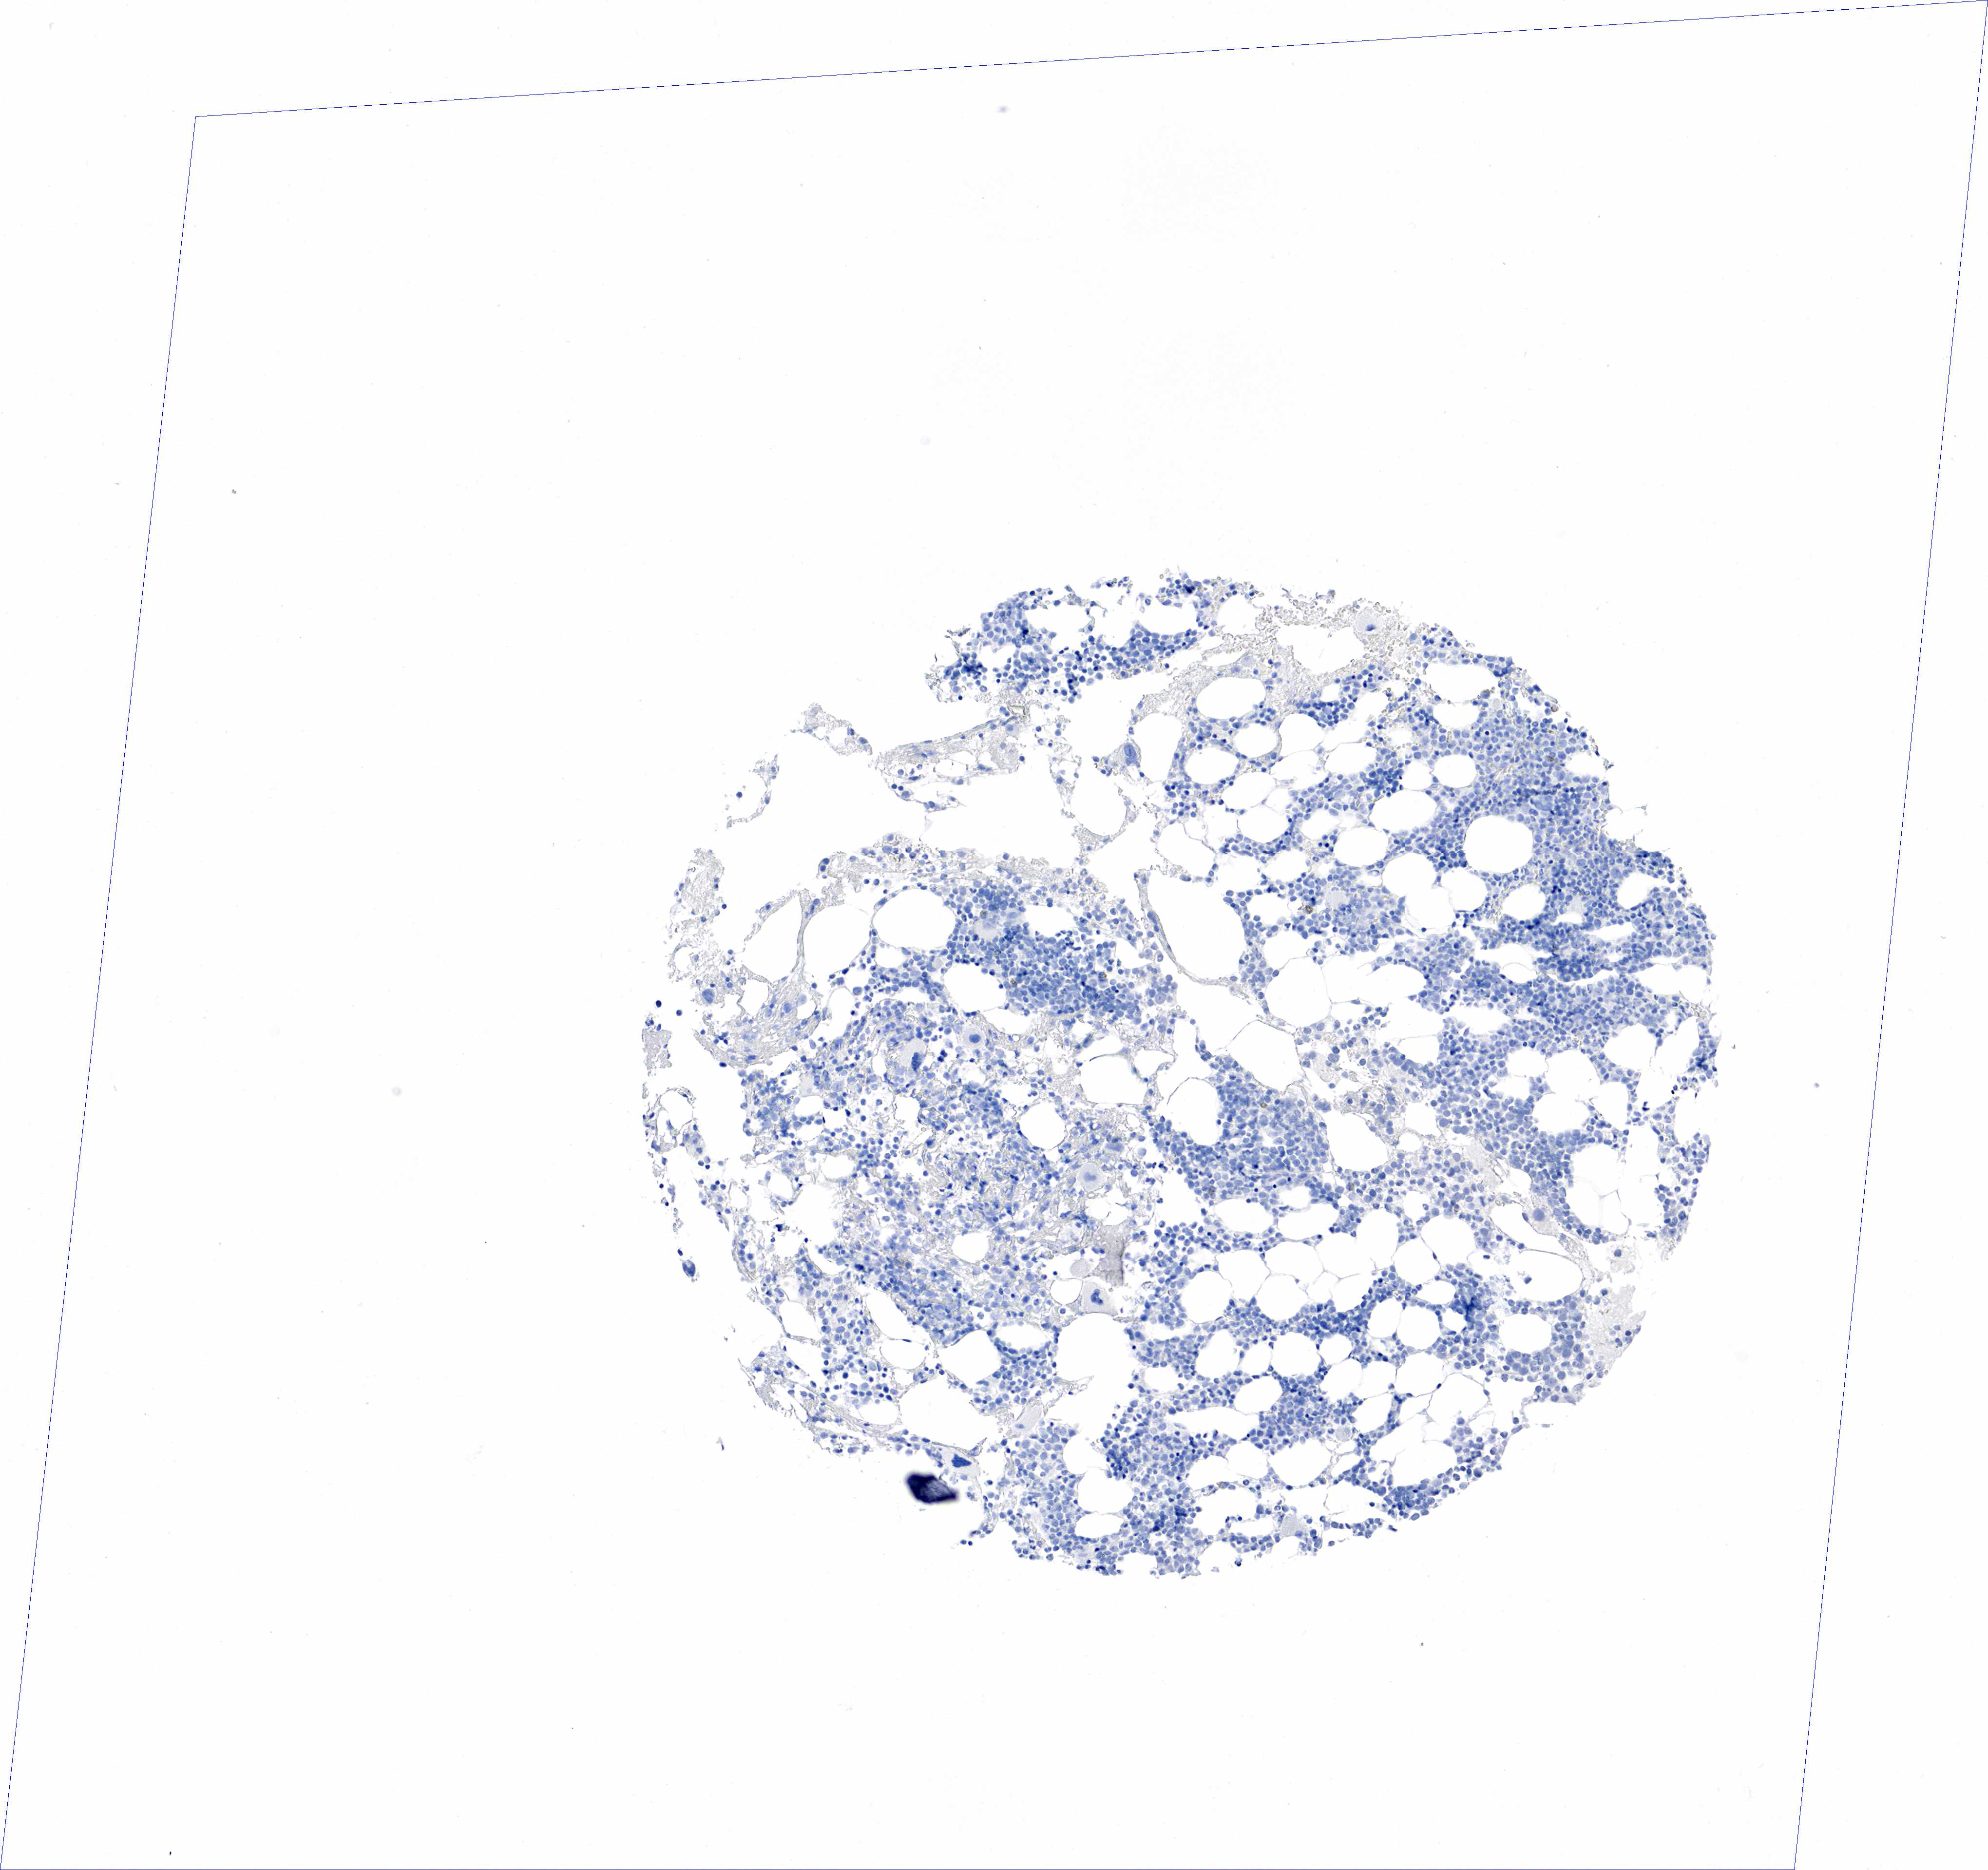

BONE MARROW - HPA RNA-seqi

The RNA-seq details section shows detailed information about the individual samples used for the transcript profiling and results of the RNA-seq analysis.

Information about each individual sample is listed below, including gender, age, a tissue section image and estimated fractions of cell types. nTPM (normalized transcripts per million) values give a quantification of the gene abundance which is comparable between different genes and samples.

N/A

Female, age 8

Bone marrow sample 99

nTPM: 0

Cell types%

Myelopoietic cells:

50

Erythropoietic cells:

30

Lymphocytes:

10

Monocytes:

5

Blastic cells: